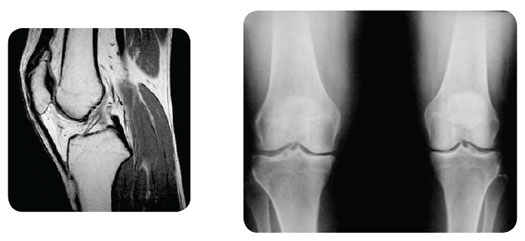

The diagnosis of osteoarthritis is usually made based upon the patient's medical history, physical examination, and X-ray findings. An MRI may be helpful in some cases to confirm the diagnosis and rule out any other conditions.